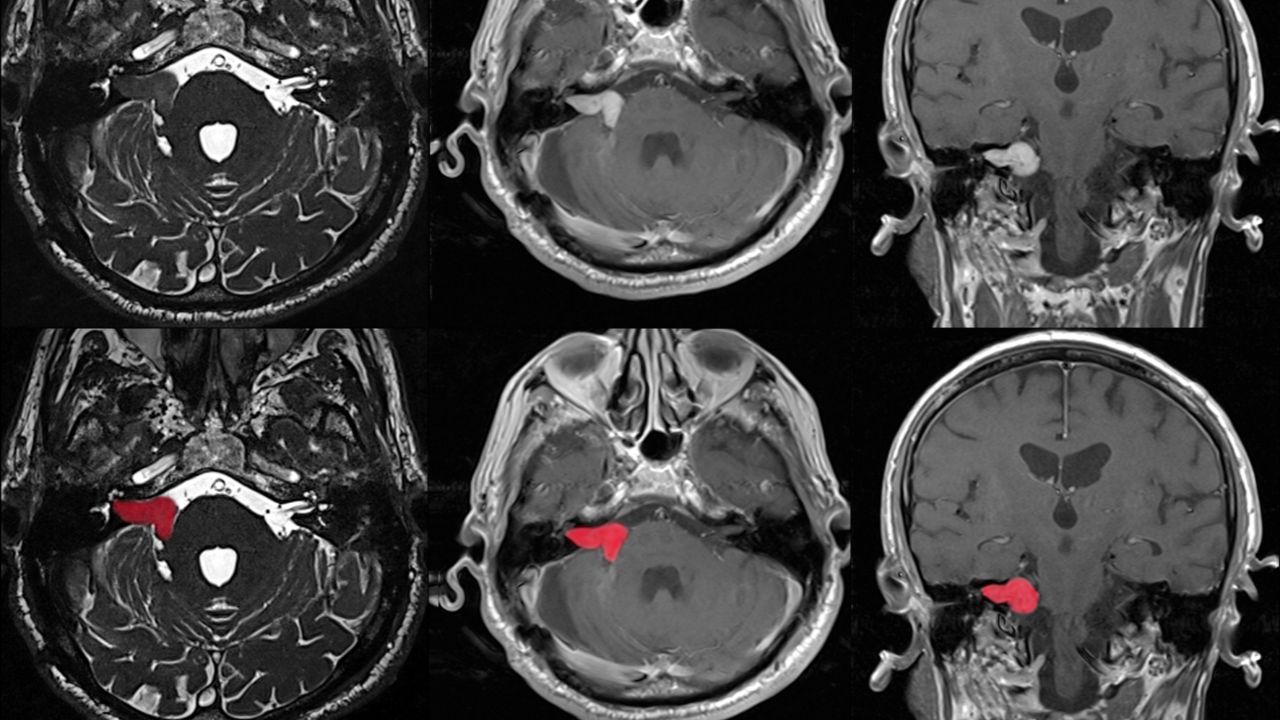

ام آر آی

در این روش از یک آهنربا قوی و امواج رادیویی، برای ایجاد نمایی دقیق و سه‌بعدی از اعصاب محیطی و بافت‌های اطراف آن‌ها استفاده می‌شود.